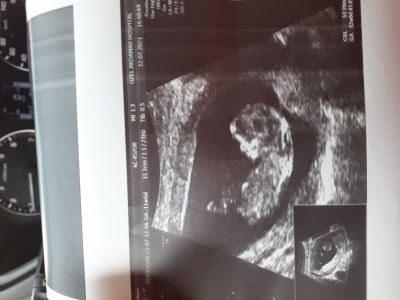

Çok hareketli, doktor cinsiyetini bir türlü göremiyor. Lütfen bakar mısınız? Her gidişimde bir umut gidiyorum

image